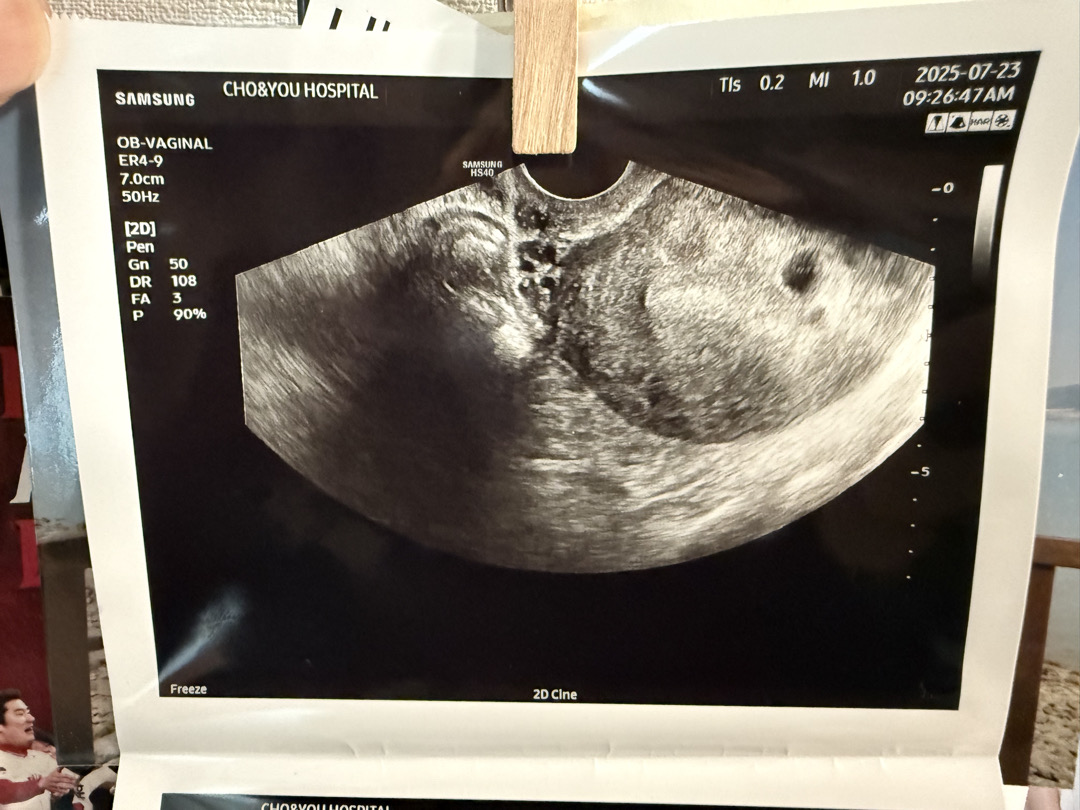

초음파 사진 기준으로 오른쪽이 제 몸 기준 오른쪽인지?? 아시는 분 있나요

오른쪽 조그만게 아기집인데요. 내 몸을 기준으로 오른손쪽에 있는 자궁에 있는걸까요?? 궁금해용..

초음파상 오른쪽 왼쪽이 자궁이랑 반대인걸로 알고 있어요!